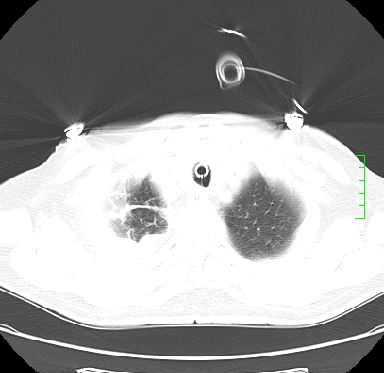

icu病人,几天都没明确诊断。m,76y,咳嗽、咳痰1周,伴气促,右胸痛入院,pe:t38.3c p135 r25 bp135/85。双肺可闻及大量湿罗音,心、腹未见明显异常。诊断:1心衰?2肺部感染?3冠心病?

9号平片

11号ct